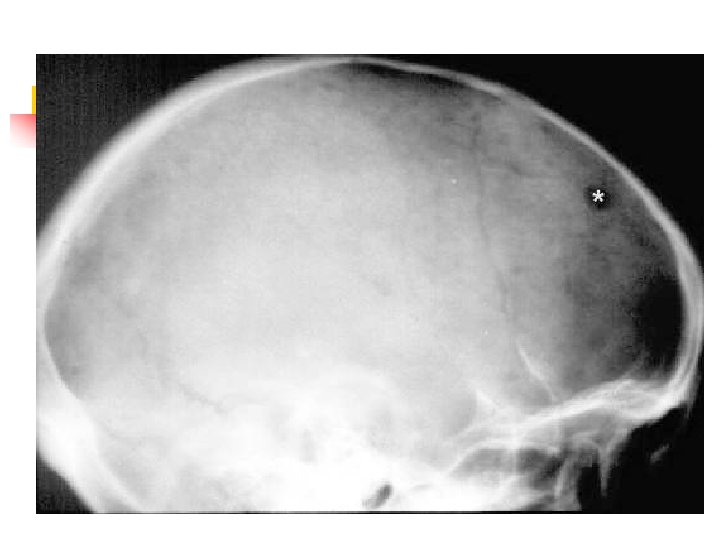

Mieloma múltiple MORFOLOGIA: n Presentación más frecuente: lesiones óseas, destructivas, multifocales. n Distribución: 1. Columna vertebral: 66% 2. Costillas: 44% 3. Cráneo: 41% 4. Pelvis: 28% 5. Fémur: 24% 6. Clavícula: 10 % 7. Escápula: 10%. n

Mieloma múltiple Comienzo de la lesión: cavidad medular= hueso esponjoso = hueso cortical. n Corte del hueso: tejido blando, rojo, gelatinoso. n Rx: lesiones en sacabocados. (1 - 4 cm). Desmineralización difusa n HISTOLOGIA: n MO: CP aumentadas (10 -90%). n